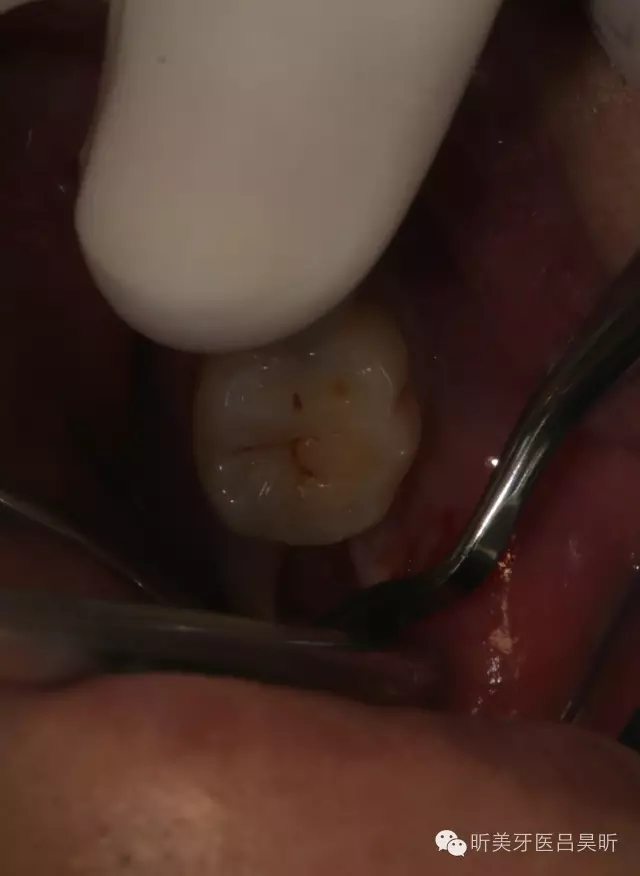

患者,男性,47缺失兩年。

術(shù)前口內(nèi)檢查,可見牙槽骨寬度良好,角化齦量適中